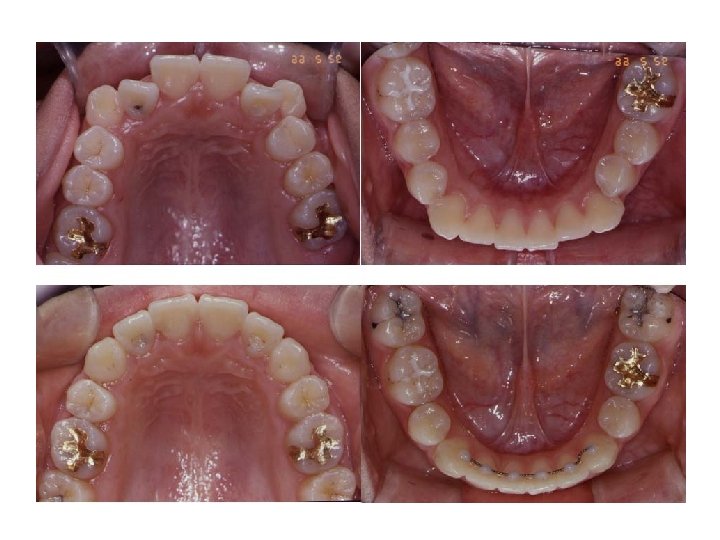

Initial Intra-oral Photographs